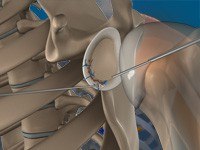

Shoulder Arthroscopy

Arthroscopy is a minimally invasive diagnostic and surgical procedure performed for joint problems. Shoulder arthroscopy is performed using a pencil-sized instrument called an Arthroscope. The arthroscope consists of a light system and camera to project images to a computer screen for your surgeon to view the surgical site. Arthroscopy is used to treat disease conditions and injuries involving the bones, cartilage, tendons, ligaments, and muscles of the shoulder joint.